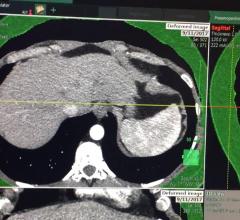

Vinodh Kumar, M.D., and Komal Shah, M.D., associate professors of radiology at MD Anderson Cancer Center, describe how ...